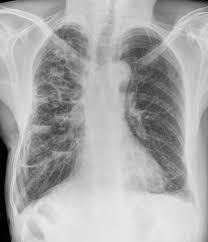

CXR features of bronchiectasis

Ring shadows

Tramlines

CXR limited sensitivity in bronchiectasis